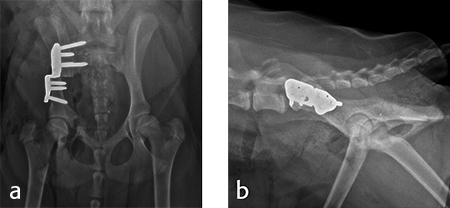

Double Triple Pelvic Osteotomy DPO TPO plate

Hip dysplasia Fitzpatrick Referrals

Triple Pelvic Osteotomy Orthopaedics WA

When Your Dog Faces Hip Dysplasia Ron Hines Vetspace 2nd Chance The Animal Health Website

The Veterinary Nurse Surgical treatment options for hip dysplasia

Product Name: Tpo hip surgery dealsAnimal Surgical Center of Michigan Veterinarian in Flint MI deals, Triple Pelvic Osteotomy Orthopaedics WA deals, Triple Pelvic Osteotomy Southwest Veterinary Surgical Service deals, Animal Surgical Center of Michigan Veterinarian in Flint MI deals, Animal Surgical Center of Michigan Veterinarian in Flint MI deals, Animal Surgical Center of Michigan Veterinarian in Flint MI deals, a Pelvic radiograph of a female performed one year after TPO. Surgery. Download Scientific Diagram deals, Double Triple Pelvic Osteotomy DPO TPO plate deals, Vet Orthopaedic Referrals Ireland fractures spine cruciate TPLO hip deals, Double Triple Pelvic Osteotomy DPO TPO plate deals, hip dysplasia triple pelvic osteotomy tpo jps Orthopaedic Referral Service fracture spine clinic joint spinal surgery arthroscopy N Ireland dog and cat veterinary specialists specialist vets deals, hip dysplasia triple pelvic osteotomy tpo jps Orthopaedic Referral Service fracture spine clinic joint spinal surgery arthroscopy N Ireland dog and cat veterinary specialists specialist vets deals, THR DPO FHO TPLO and TTA How to Talk to Your Veterinarian About Orthopedic Surgery The Animal Medical Center deals, Hip Dysplasia Oakdale Veterinary Group deals, Hip Dysplasia Hip Conditions in Dogs Surgery Costs deals, hip dysplasia triple pelvic osteotomy tpo jps Orthopaedic Referral Service fracture spine clinic joint spinal surgery arthroscopy N Ireland dog and cat veterinary specialists specialist vets deals, Animal Surgical Center of Michigan Veterinarian in Flint MI deals, Double Triple Pelvic Osteotomy DPO TPO plate deals, Vet Orthopaedic Referrals Ireland fractures spine cruciate TPLO hip deals, Total Hip Replacement A Complete Information Guide by Russell Kalis DVM DACVS SA AVES deals, Hip Dysplasia in dogs and cats Long Beach Animal Hospital deals, Hip dysplasia Fitzpatrick Referrals deals, Frontiers The Use of Sixty Degree Rotation of the Acetabulum for Treatment of Dogs With Canine Hip Dysplasia. A Short Case Series deals, THR DPO FHO TPLO and TTA How to Talk to Your Veterinarian About Orthopedic Surgery The Animal Medical Center deals, Double Triple Pelvic Osteotomy DPO TPO plate deals, Hip dysplasia Fitzpatrick Referrals deals, Triple Pelvic Osteotomy Orthopaedics WA deals, When Your Dog Faces Hip Dysplasia Ron Hines Vetspace 2nd Chance The Animal Health Website deals, The Veterinary Nurse Surgical treatment options for hip dysplasia deals, Hip dysplasia when do we consider surgery deals, Tpo shop dog surgery deals, Vet Orthopaedic Referrals Ireland fractures spine cruciate TPLO hip deals, Royal Orthopaedic Hospital Triple Pelvic Osteotomy TPO deals, Hip dysplasia when do we consider surgery Vet Times deals, Femoral Head and Neck Excision Arthroplasty Arizona Canine Orthopedics Sports Medicine deals.